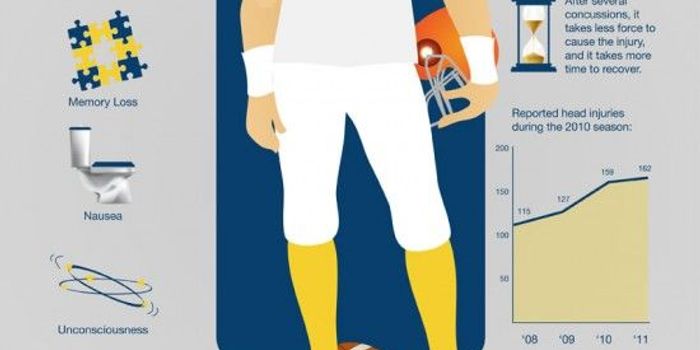

SEP 12, 2017VideosHelmets are the norm in contact sports like American football. But here's the thing, helmets can't stop the brain from " ...

NOV 27, 2017VideosWhile the problem of Chronic Traumatic Encephalopathy (CTE) is well known in NFL players, the risks to hockey players in ...

NOV 20, 2017VideosChronic Traumatic Encephalopathy, known as CTE, is a constant focus for NFL players. The repeated blows to the head that ...

NOV 13, 2017VideosAfter his death by suicide, former NFL player Aaron Herandez's family announced that his brain would be donated to the C ...